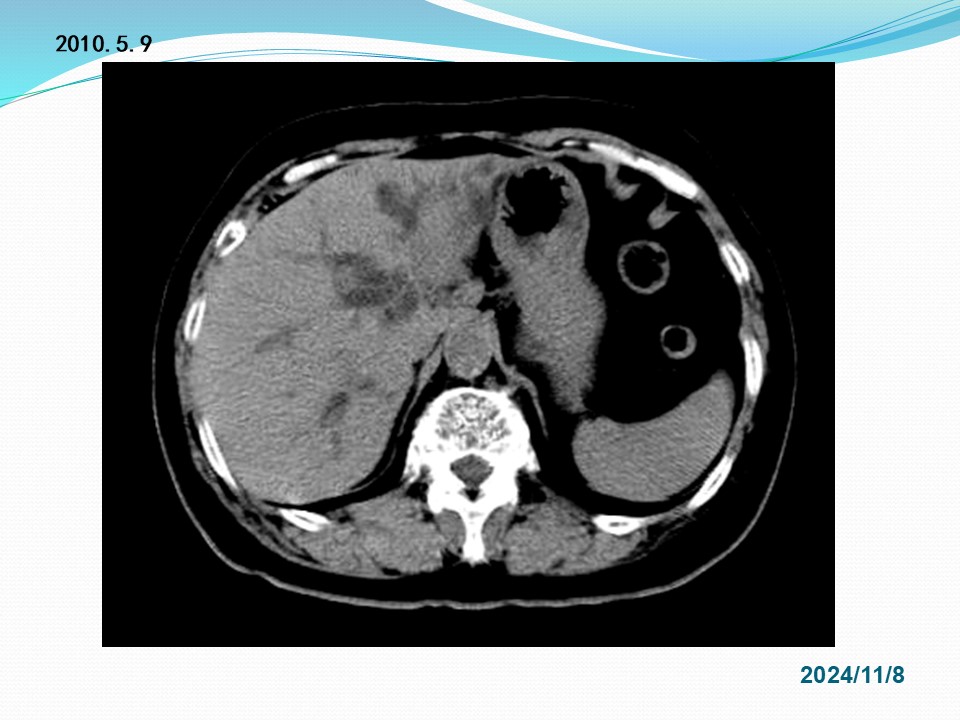

胆管癌外科治疗的实践和存在问题的探讨

Biliary duct cancer / Cholangiocarcinoma

定义:发生于肝外胆管(含左右肝管主干至胆总管下端)恶性肿瘤的总称。不包括肝内胆管癌、肝脏胆管细胞癌、胆囊癌、乏特壶腹癌。